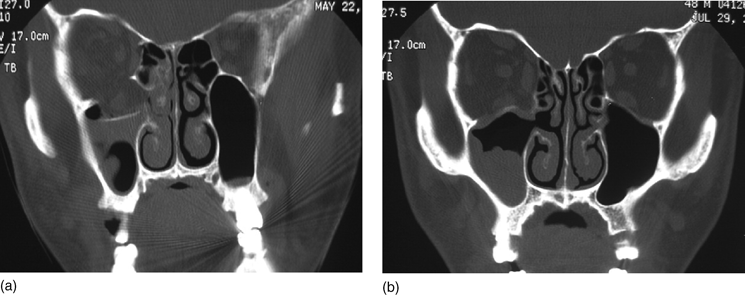

Pediatric Orbital Fractures Sciencedirect